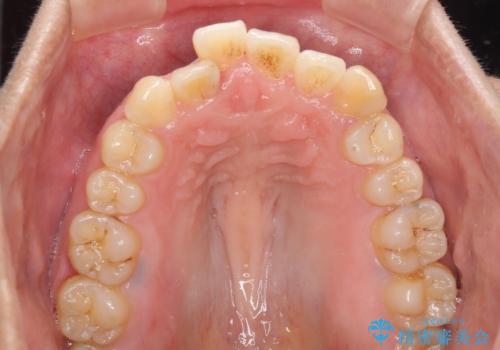

- 上下のデコボコを改善したいとのことで来院された患者様です。

近々妊娠する予定であり、極力短期間で治療したいとのことで、ワイヤー装置による非抜歯矯正治療を行うこととしました。

治療開始後すぐに妊娠され、つわりと闘いながらの矯正治療となりました。

上下顎でゴムかけを行ったのですが、早く終わらすためにしっかりと装着していただき、無事出産前に装置を外すことができました。